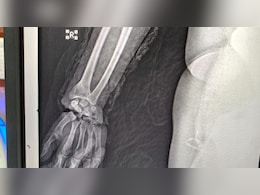

जोधपुर AIIMS ने युवक के दोनों कटे हाथों को जोड़ा, 12 घंटे तक चला ऑपरेशन

27 सितम्बर 2025, ऑपरेशन के दसवें दिन, मरीज की हालत पूरी तरह स्थिर है. दाएं हाथ की उंगलियों में रक्त संचार सामान्य रूप से हो रहा है और हड्डियों का जुड़ना व फिजियोथेरेपी की प्रक्रिया जारी है.